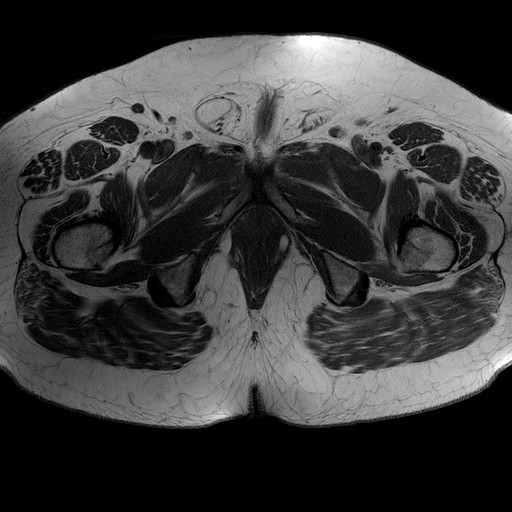

Esami: RMN BACINO

T1W_TSE

Evidenti e simmetriche alterazioni osteofitosiche in regione coxo femorale con riduzione delle rime articolari. Degenerazione completa del cercine glenoideo. Non attuali segni di versamento articolare. Non segni di edema osseo che escludono attuale algodistrofia od osteonecrosi. Lieve e simmetrica riduzione del trofismo della muscolatura glutea.